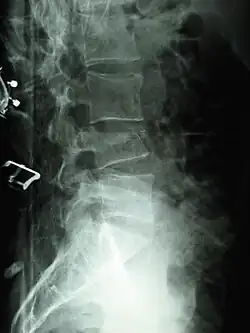

A compression fracture is a collapse of a vertebra. It may be due to trauma or due to a weakening of the vertebra (compare with burst fracture). This weakening is seen in patients with osteoporosis or osteogenesis imperfecta, lytic lesions from metastatic or primary tumors,[1] or infection.[2] In healthy patients, it is most often seen in individuals suffering extreme vertical shocks, such as ejecting from an ejection seat. Seen in lateral views in plain x-ray films, compression fractures of the spine characteristically appear as wedge deformities, with greater loss of height anteriorly than posteriorly and intact pedicles in the anteroposterior view.[3]

Compression fractures are usually diagnosed on spinal radiographs, where a wedge-shaped vertebra may be visible or there may be loss of height of the vertebra. In addition, bone density measurement may be performed to evaluate for osteoporosis. When a tumor is suspected as the underlying cause, or the fracture was caused by severe trauma, CT or MRI scans may be performed.

X-ray of the lumbar spine with a compression fracture of the third lumbar vertebra. -